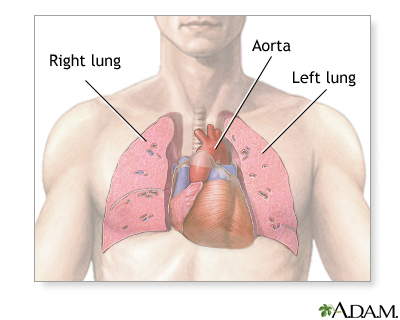

A chest CT (computed tomography) scan is an imaging method that uses x-rays to create cross-sectional pictures of the chest and upper abdomen.

A CT scan quickly creates detailed pictures of the body. The test may be used to get a better view of the structures inside the chest. A CT scan is one of the best ways of looking at soft tissues such as the heart and lungs.

- To determine the size, shape, and position of organs in the chest and upper abdomen